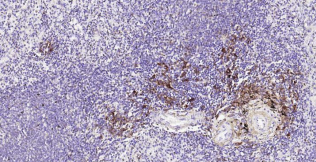

HLA-DR, like other MHC class II molecules, is a transmembrane glycoprotein composed of a 36 kDa alpha chain (DRA) and 27 kDa beta chain (DRB). The alpha chain gene contains 5 exons. Exon 1 encodes the leader peptide, exons 2 and 3 encode the two extracellular domains, and exon 4 encodes the transmembrane domain and the cytoplasmic tail. DRA does not have polymorphisms in the peptide binding part and acts as the sole alpha chain for DRB1, DRB3, DRB4 and DRB5. Within the DR molecule the beta chain contains all the polymorphisms specifying the peptide binding specificities. Hundreds of DRB1 alleles have been described and typing for these polymorphisms is routinely done for bone marrow and kidney transplantation. HLA-DR is expressed primarily on antigen presenting cells such as B lymphocytes, monocytes, macrophages, thymic epithelial cells and activated T lymphocytes. Three loci, DR, DQ and DP, encode the major expressed products of the human class II region. The human MHC class II molecules bind intracellularly processed peptides, present them to T-helper cells, and have a critical role in the initiation of the immune response.

| 12 | Control slide (Human spleen) | 1 slide | RTU | RT |